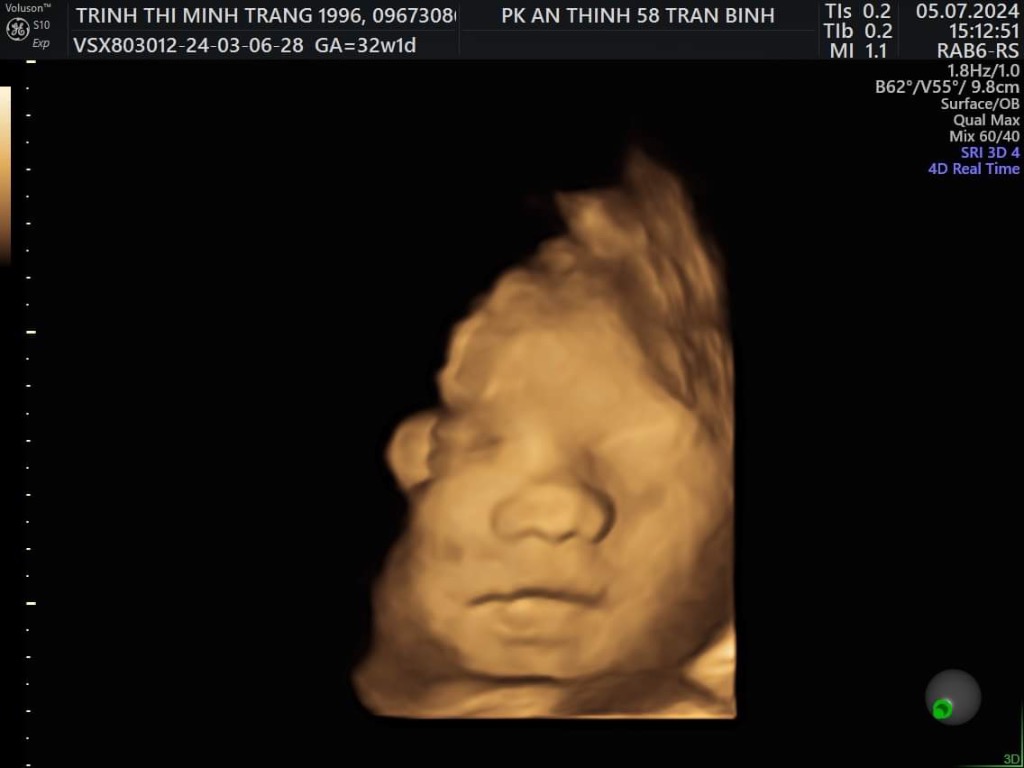

Trịnh Thị Minh Trang